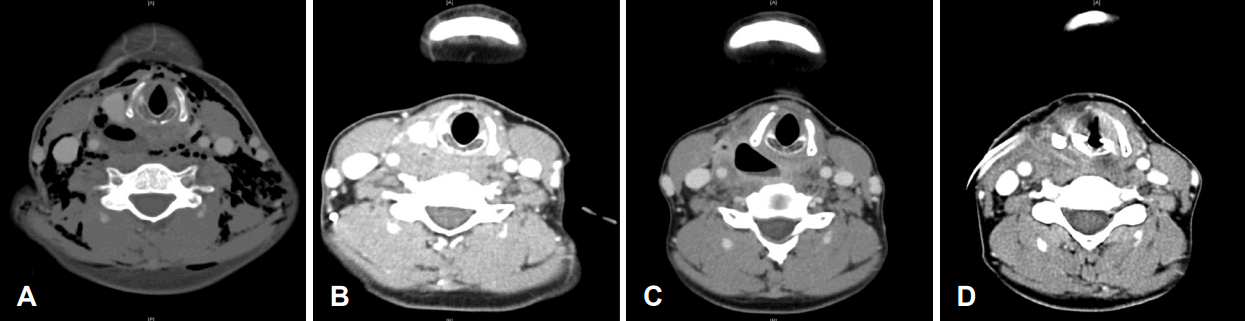

Neck contrast enhanced CT images. A: Extensive subcutaneous emphysema immediately after the esophagogastroduodenoscopy (EGD). B: Markedly decreased air pocket near cricoid cartilage 2 months after EGD. C: Increased size of air pocket near right cricoid cartilage which means persistent perforation. D: No abnormality after the endoscopic and open surgery with regional flap reconstruction.

A contrast enhanced CT scan of the neck and thorax revealed extensive subcutaneous emphysema and pneumomediastinum (Fig. 2A), with a suspicious air bubble observed in the area around the right side of the hypopharynx. A physical examination revealed crepitus in the neck and chest area, along with right-sided neck pain, but no subjective respiratory distress.

On esophagography, contrast leakage was found (Fig. 3A). Since the perforation of the hypopharynx was made iatrogenic and the patient preferred conservative management rather than external surgical approach, she was first treated with conservative treatment. Empirical antibiotics (ampicillin/sulbactam) combined with prohibition of oral intake was prescribed. One month after the event, the subcutaneous emphysema spontaneously resolved and minimal pooling of contrast in cervical esophagus without definite leakage was observed on esophagography (Fig. 3B). Two months after perforation, a small air pocket was seen but markedly decreased on neck CT (Fig. 2B). At that time, she was discharged in a condition where subcutaneous emphysema did not worsen, and oral intake was possible.

One week after discharge, she experienced worsening neck discomfort, and CT scan revealed an increase in the size of the previously observed air pocket (Fig. 2C).

The patient progressed to a regular diet on the 7th day after surgery, based on the confirmation of no contrast leakage on esophagography and no abnormality on Neck CT (Fig. 3C and 2D). She had tolerable oral diet until last follow-up at 6 months after the last surgery.